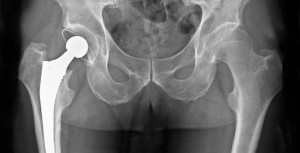

Reemplazo total de cadera o entrenamiento de resistencia para la osteoartritis grave de cadera

En un ensayo clínico que comparó el reemplazo total de cadera con el entrenamiento de resistencia en pacientes con osteoartritis de cadera grave y con indicación de cirugía, el reemplazo de cadera condujo a una mayor reducción del dolor y una mejor función a los 6 meses. New England Journal of Medicine, 30 de octubre de 2024.